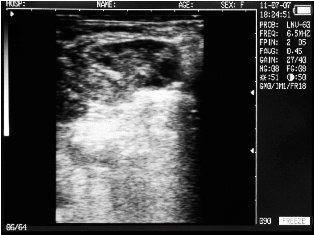

Ultrasound images of cows reproductive system, generated by a scanner Sonovet with rectal linear transducer.

Filled bladder cow